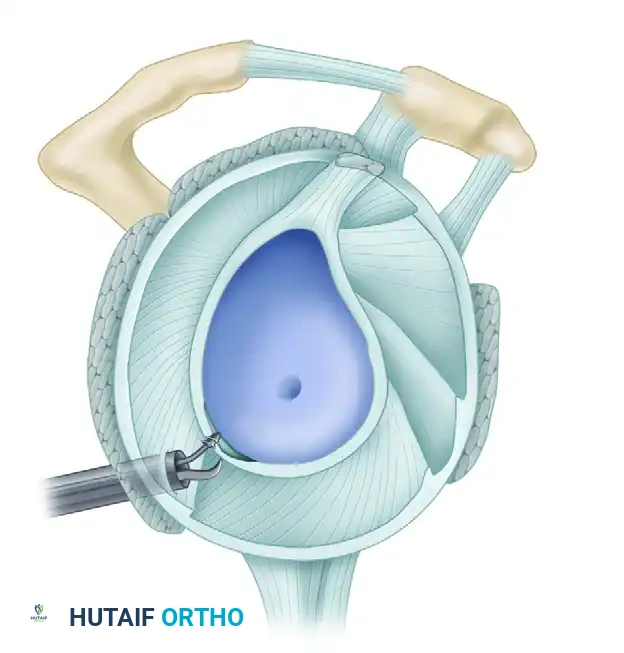

The arthroscopic Bankart repair remains the cornerstone surgical intervention for recurrent anterior glenohumeral instability. The classic Bankart lesion—an avulsion of the anteroinferior capsulolabral complex from the glenoid rim—disrupts the primary static stabilizer of the shoulder: the inferior glenohumeral ligament (IGHL). Successful surgical management requires not merely the reattachment of the labrum, but the anatomical restoration of capsular tension, the elimination of pathological volume (the "drive-through" sign), and the recreation of a robust anterior soft-tissue bumper.

Optimal visualization and access to the inferior capsule dictate meticulous patient positioning. The lateral decubitus position is preferred by many master surgeons for its superior access to the inferior and posterior compartments.

- Traction: Place the operative arm in a specialized traction sleeve. Suspend the arm in 45 degrees of abduction and 20 degrees of forward flexion using 10 to 12 lbs of traction. This specific vector distracts the joint orthogonally, opening the anteroinferior working space without placing undue tension on the axillary nerve.

The Four-Quadrant Portal Approach

After identifying the quadrants of injury, create the planned working portals using outside-in spinal needle localization to ensure optimal trajectory.

A, In the superior quadrant, SLAP tears between 2 and 10 o’clock are accessible through the anterior portal (AP), anterosuperior lateral (ASL), and the portal of Wilmington (PW).

B, In the anterior quadrant, anteroinferior labral tears are accessible through the anterior portal (AP) and the 5-o’clock portal.

C, In the anteroinferior quadrant, anteroinferior capsulolabral tears are accessible through the 5- and 7-o’clock portals.

D, In the posteroinferior quadrant, posterior labral tears can be accessed through the 7-o’clock portal.

- Anterosuperior Portal: Enter just posterior to the biceps tendon and anterior to the leading edge of the supraspinatus tendon. This is the optimal viewing portal to visualize the full extent of capsuloligamentous damage.

- Anterior Central Portal: Place an 8.25-mm clear threaded cannula just above the superior edge of the subscapularis tendon, angled at approximately 45 degrees to the glenoid articular surface. This is the primary working portal for anchor placement and suture passing.

- 5-o'clock Percutaneous Portal: Essential for placing the most inferior anchor at the 5:30 position.

- 7-o'clock Posterior Portal: If the lesion extends posteriorly, establish this portal via spinal needle localization to address posteroinferior pathology.